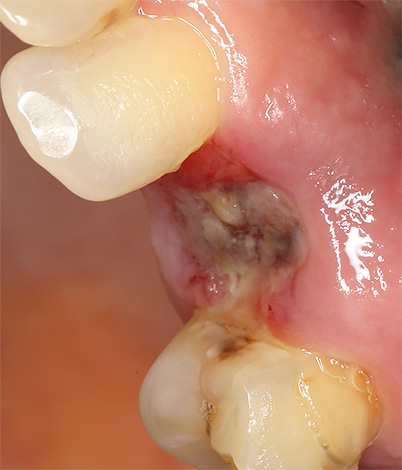

A infecção do poço geralmente ocorre durante a remoção complexa, quando resíduos cariados do dente doente são jogados profundamente na ferida, o que causa sua supuração. Na maioria dos casos, após a extração desse dente, as gengivas e a cavidade cicatrizam por um período muito longo.

No entanto, é importante observar o fato de que o processo purulento no orifício também pode ocorrer como resultado de um tratamento inadequado da ferida pelo próprio paciente: nesse caso, a infecção não entra durante o procedimento de remoção, mas após o mesmo. Quando o alimento constantemente entra no buraco e se acumula por um longo tempo junto com as bactérias da cavidade oral, pode ocorrer supuração da ferida e sua cicatrização é significativamente atrasada.

Como resultado da ligação da infecção à ferida, pode ocorrer alveolite - inflamação do orifício após a extração do dente, que geralmente se desenvolve 1-3 dias após o procedimento. Nesse caso, a dor aguda ocorre na área do dente extraído, a cicatrização normal do orifício é perturbada (uma respiração putrefativa desagradável também é frequentemente observada).

O resultado de um processo inflamatório purulento é a longa cicatrização das gengivas, que, além disso, determina o risco de desenvolver uma complicação grave - osteomielite limitada da mandíbula.